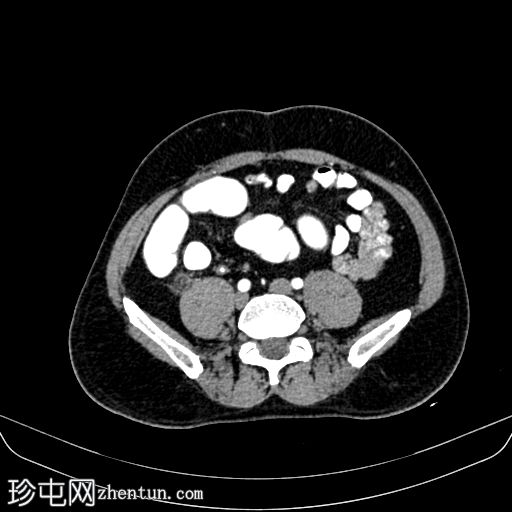

轴位

平扫

平扫CT显示,盲肠后外侧壁旁可见一边界清晰的卵圆形脂肪密度影,周围环绕一薄层高密度环(“高密度环”)。周围脂肪间隙轻度改变,无游离液体,邻近结肠壁未见增厚。动脉期,病灶仍为脂肪密度影,高密度环略有强化;未见动脉出血。

门静脉期,可见一持续存在的脂肪密度影,周围环绕高密度环;周围脂肪条索状改变,无脓肿形成,邻近结肠无憩室,盲肠壁正常。无阑尾炎,无淋巴结肿大,无游离气体或液体。